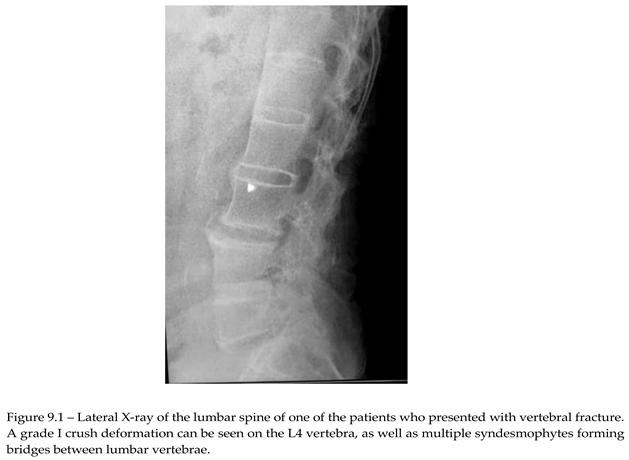

Of the 76 patients with SpA that presented for REMS evaluation, 2 had recent vertebral fracture, one classified as grade I wedge modification on the Genant scale affecting T8 vertebra. Imagistics done during clinical practice for these patients didn’t show any structural modification related to AxSpA. The other patient had a grade I crush deformity on L4 vertebra, X-ray showing multiple syndesmophytes in the lumbar area (Image 9.1).

No significant differences were seen when comparing hip sites, neither in regards to DXA vs REMS analysis, nor between the control group and SpA group after REMS measurement (2-sample T-test, p<0.005). We analyzed the differences between younger (under 45 yo) and older individuals (over 45 yo), comparing their BMD values measured with REMS (graph 9.2), where we found that younger patients with SpA have lower BMD values compared to their equivalent age controls. This might suggest that bone loss is present from the onset of the disease and can go unrecognized until classification criteria are met. This finding can explain the two patients described anteriorly that presented directly with vertebral fractures, with no other clinical manifestations suggestive of SpA.